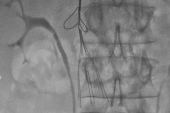

IVC filters are used to prevent pulmonary embolism (PE) in patients with venous thromboembolism (VTE) and contraindications to anticoagulation, as well as those who have failed anticoagulation. In the US, it’s estimated that nearly 40,000 IVC filters are placed annually, with nearly one in six Medicare beneficiaries with PE receiving a filter.

In 2010 and 2014, the US Food and Drug Administration issued safety communications that advised physicians to remove IVC filters as soon as clinically feasible. The devices are meant to be taken out once the patient’s risk of PE subsides because there can be complications, such as filter fracture or device embolization, if they are left in place too long.